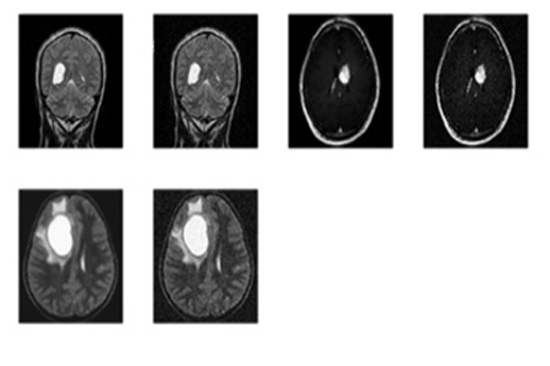

- Step-2: The MRI images were procured from BITE (Brain Images of Tumors for Evaluation database) by the NeuroImaging and Surgical Technologies Lab [7] as shown in Fig. (1).

To check functionality of the proposed work for the detection of brain cancer in MRI images using HMM classifier, a set of 6 images was obtained from BITE database. All images were processed to extract cancerous portion using HMM (Hidden Markov Model) classifier and then the corresponding parameters such as accuracy, Mean Square Error (MSE), Peak Signal- to- Noise Ratio (PSNR) and fault rate dust detection were calculated for detection using the HMM classifier. So when the code was run and an appropriate image was selected for the intended task of cancer detection and extraction of the abnormal portion, the first output was the figure showing input MRI image and the corresponding filtered image using subplot command to display them at position (1, 2, 1) and (1, 2, 2) respectively.

The following figures show the output of Brain Cancer Detection. The image fed as input for brain cancer detection is shown in Figs. (1-7).

The respective filtering output is shown in Fig. (2).